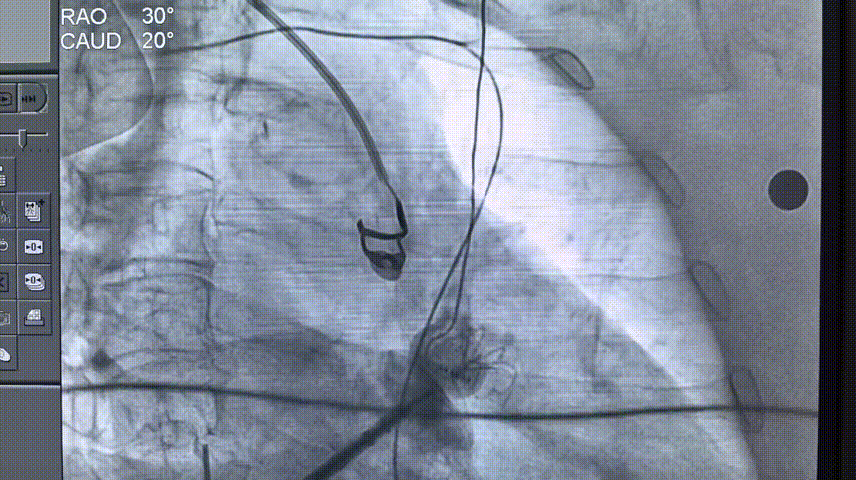

左心耳造影及测量:RAO30,CAUD20测量锚定区22.79mm,开口区31.68mm。

左心耳造影及测量

ICE下测量锚定区22.31mm,开口区28.73mm,选择LAMax 2436 Plus型号封堵器。